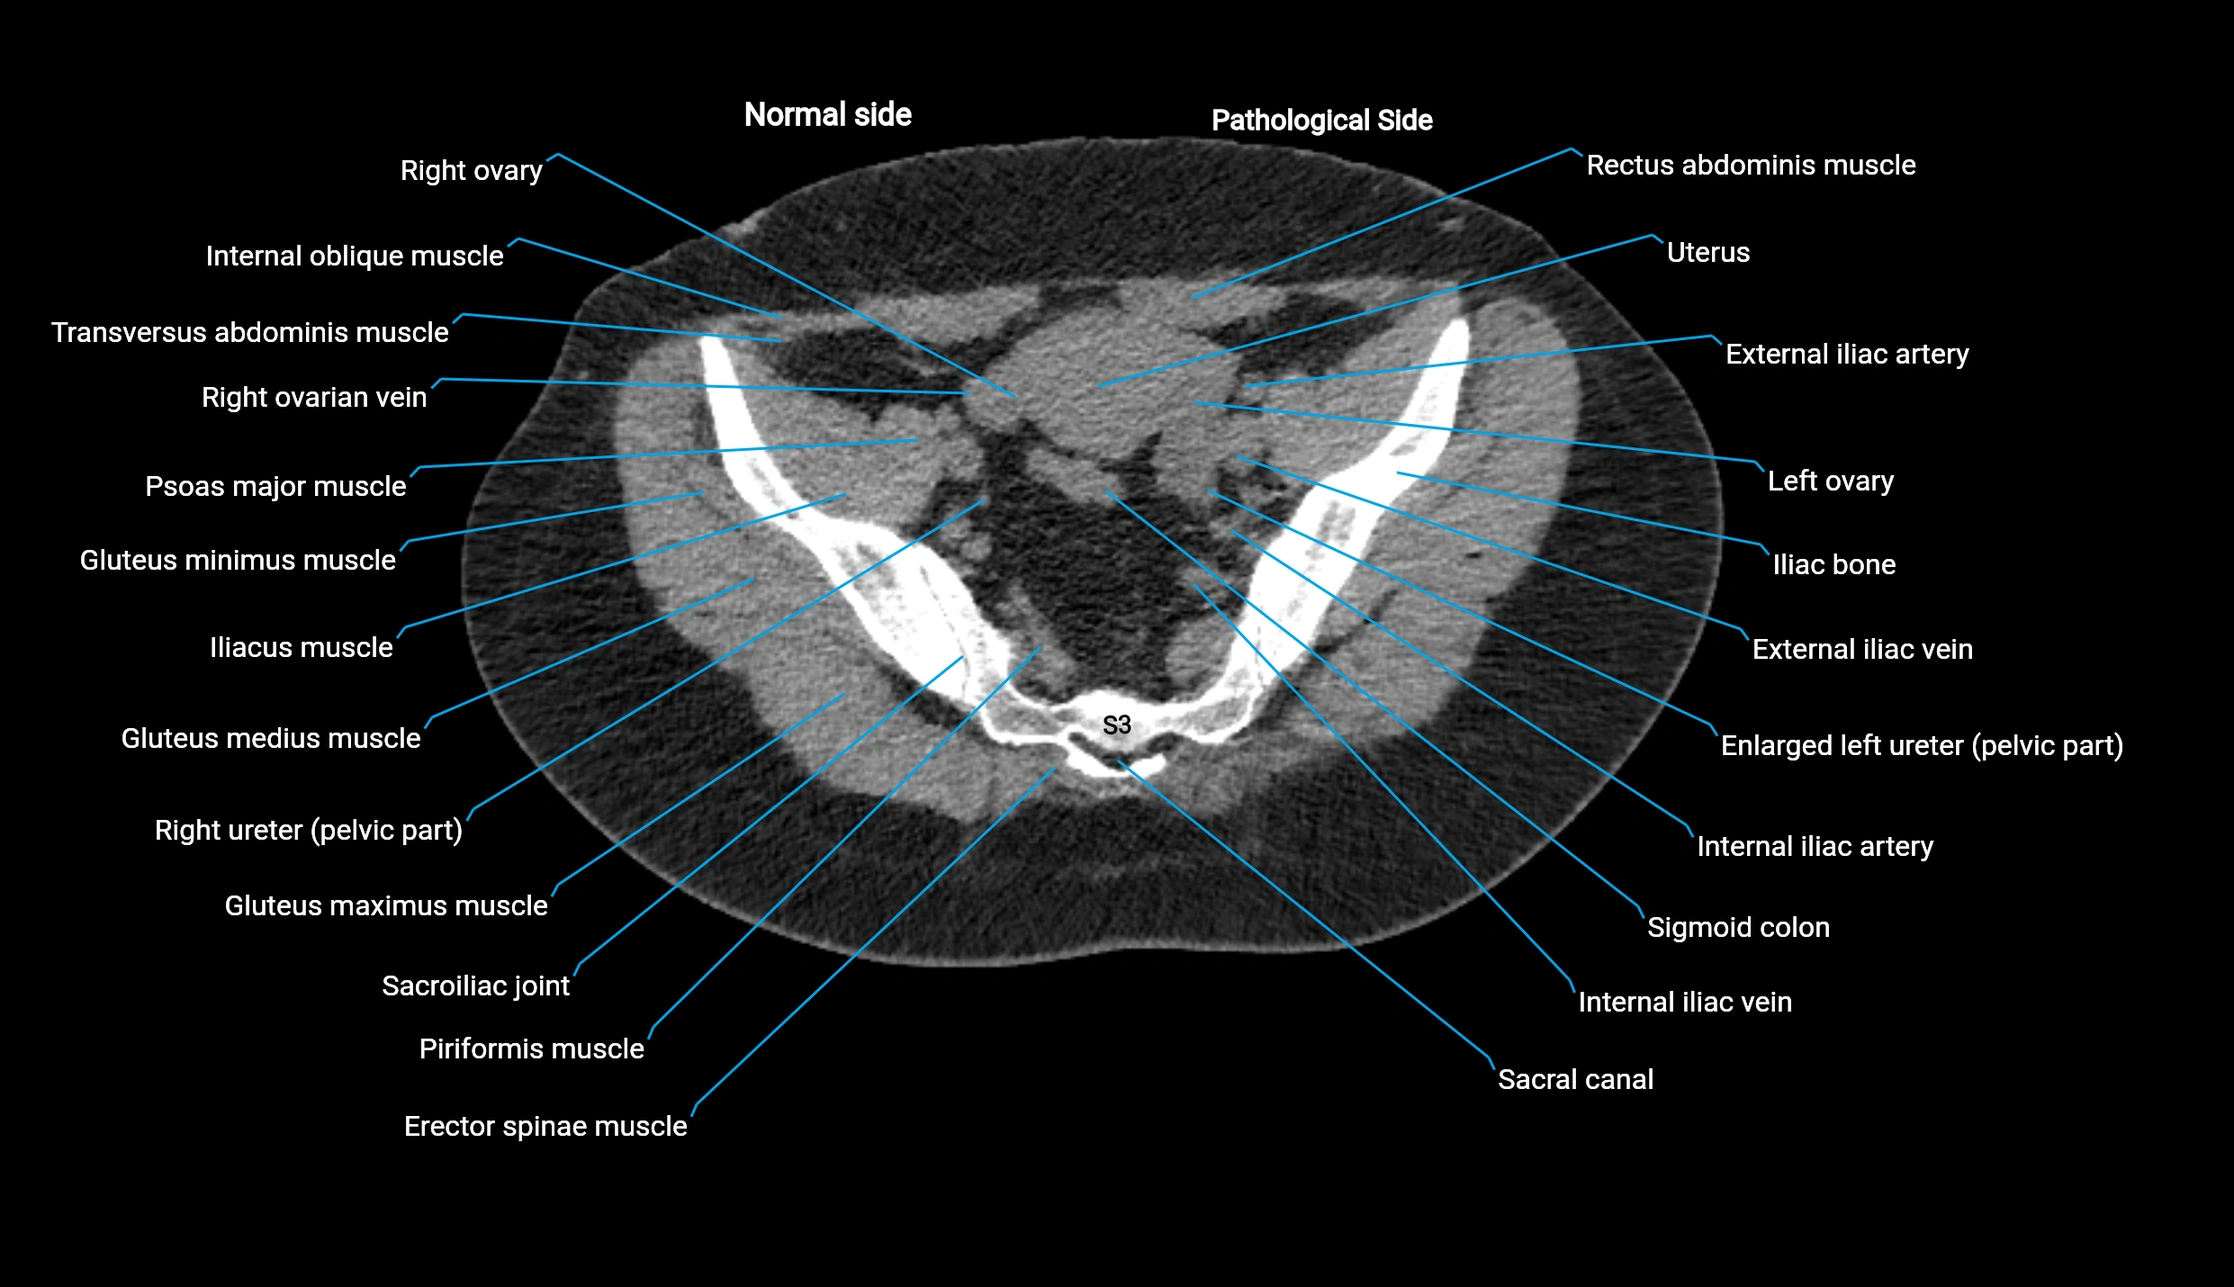

CT image

image